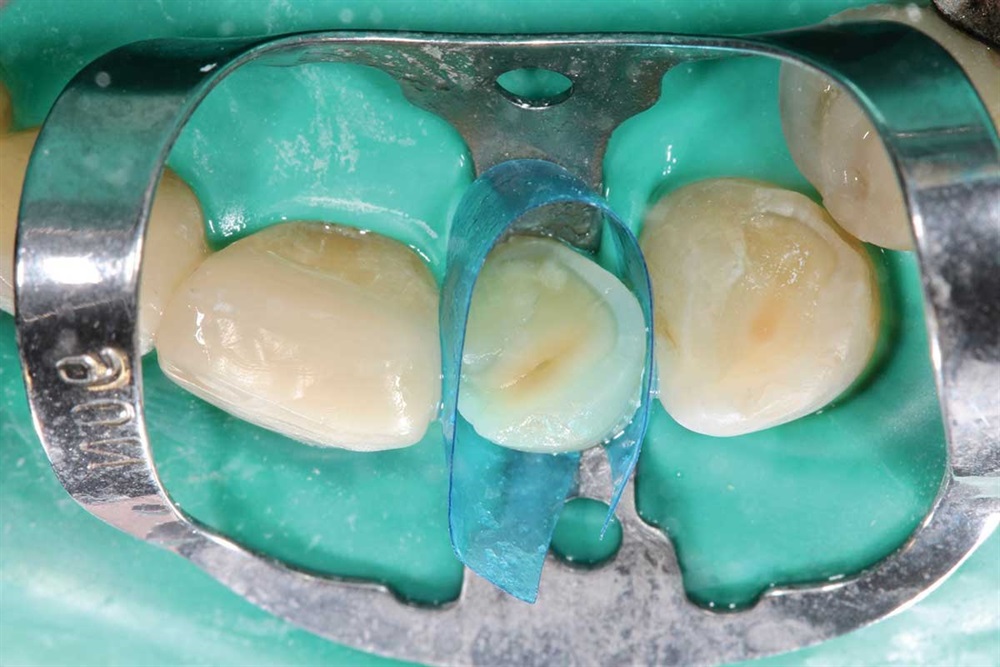

Show Your Work

Fig. 28: My first increment is Z250 to provide palatal support, and then I cover that with Renamel A1.5.

Fig. 29: I cut an increment off the end of my Renamel syringe, flatten it between my finger and thumb and place on the labial of the tooth. I apply a little bonding resin on the composite increment to reduce pull-back, then work it into the interproximal and cover the tooth. Takes some time, because it does not flow like Z250.